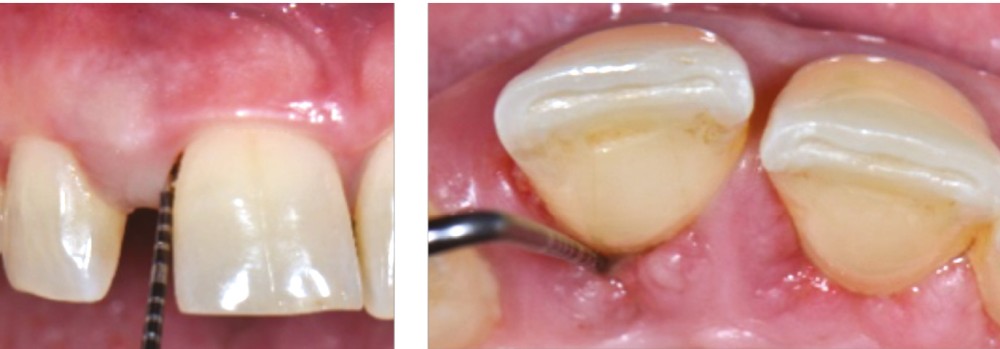

La migration dentaire pathologique est un déplacement dentaire provoqué lorsque l’équilibre entre les forces qui maintiennent la position physiologique de la dent et les forces qui tendent à la déplacer est rompu [1]. Selon la quantité de perte d’attache, de simples forces occlusales ou la poussée linguale lors de la déglutition suffisent à déplacer la dent.

La MDP est une complication fréquente des parodontites et parfois l’un de ses premiers signes cliniques visibles par le patient et son entourage. Sa prévalence est de 30 à 55 % chez les patients atteints de parodontites modérées et sévères [2].

La MDP est dépendante de l’axe des forces appliquées à la dent. Ces forces peuvent ainsi conduire à des déplacements horizontaux, des versions (basculement par rotation) et/ou des égressions/extrusions (déplacement vertical seul, souvent retrouvé lors de la perte de dent antagoniste).

Des combinaisons de mouvements sont le plus souvent retrouvées, notamment lors de la perte du calage postérieur : déplacement horizontal et vertical, migration « en éventail ».